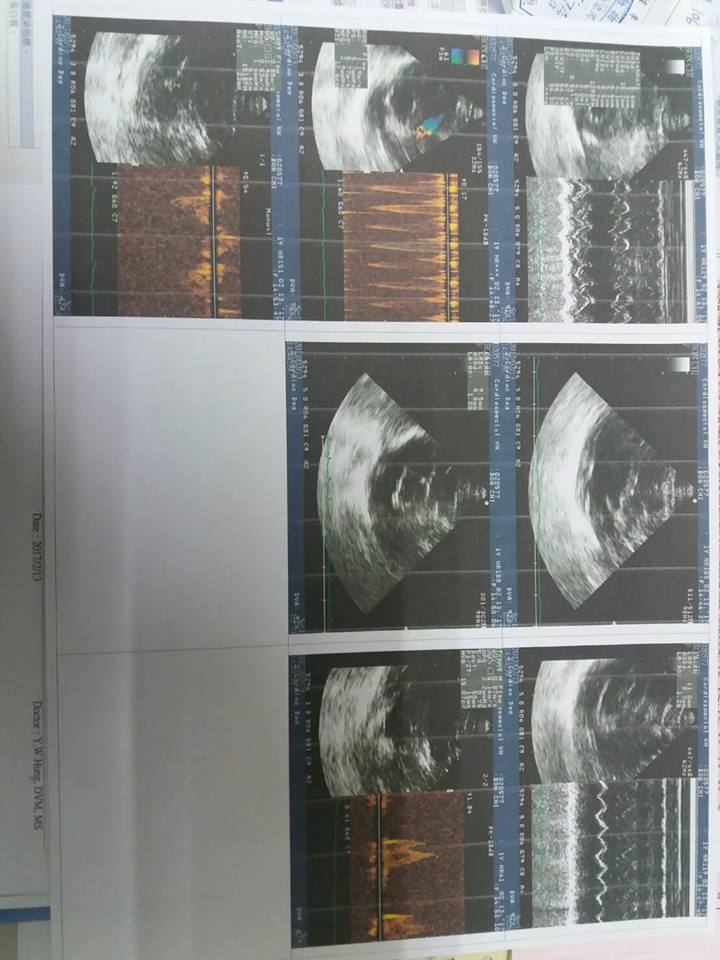

以下為本次的回診資料

2/13專心回診-罔市 4.9KG

【回診狀況】

今日量血壓130-140,正常

原先希望在最佳狀態下,罔市可以不用吃藥,但今日心超下,

罔市的左心室有稍微變小,19.4-->14.6,

但是右心室仍維持不變,

因此無法停藥,需繼續吃

今日參考罔市於1/25極光的血檢報告,發現罔市紅血球濃度太高,水分攝取不足(醫生是建議關籠觀察,但我方也有提及是否可直接灌水則不需整天關籠,此部分則需再討論)